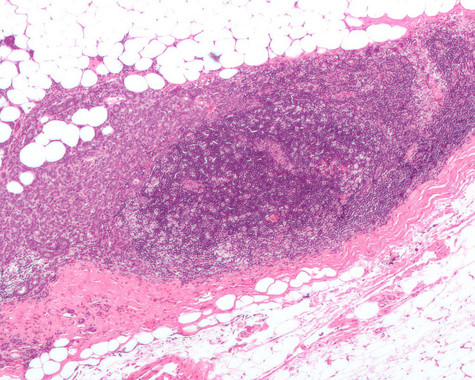

Ganglio linfático invadido por carcinoma de mama ductal. (Foto: Wikipedia)